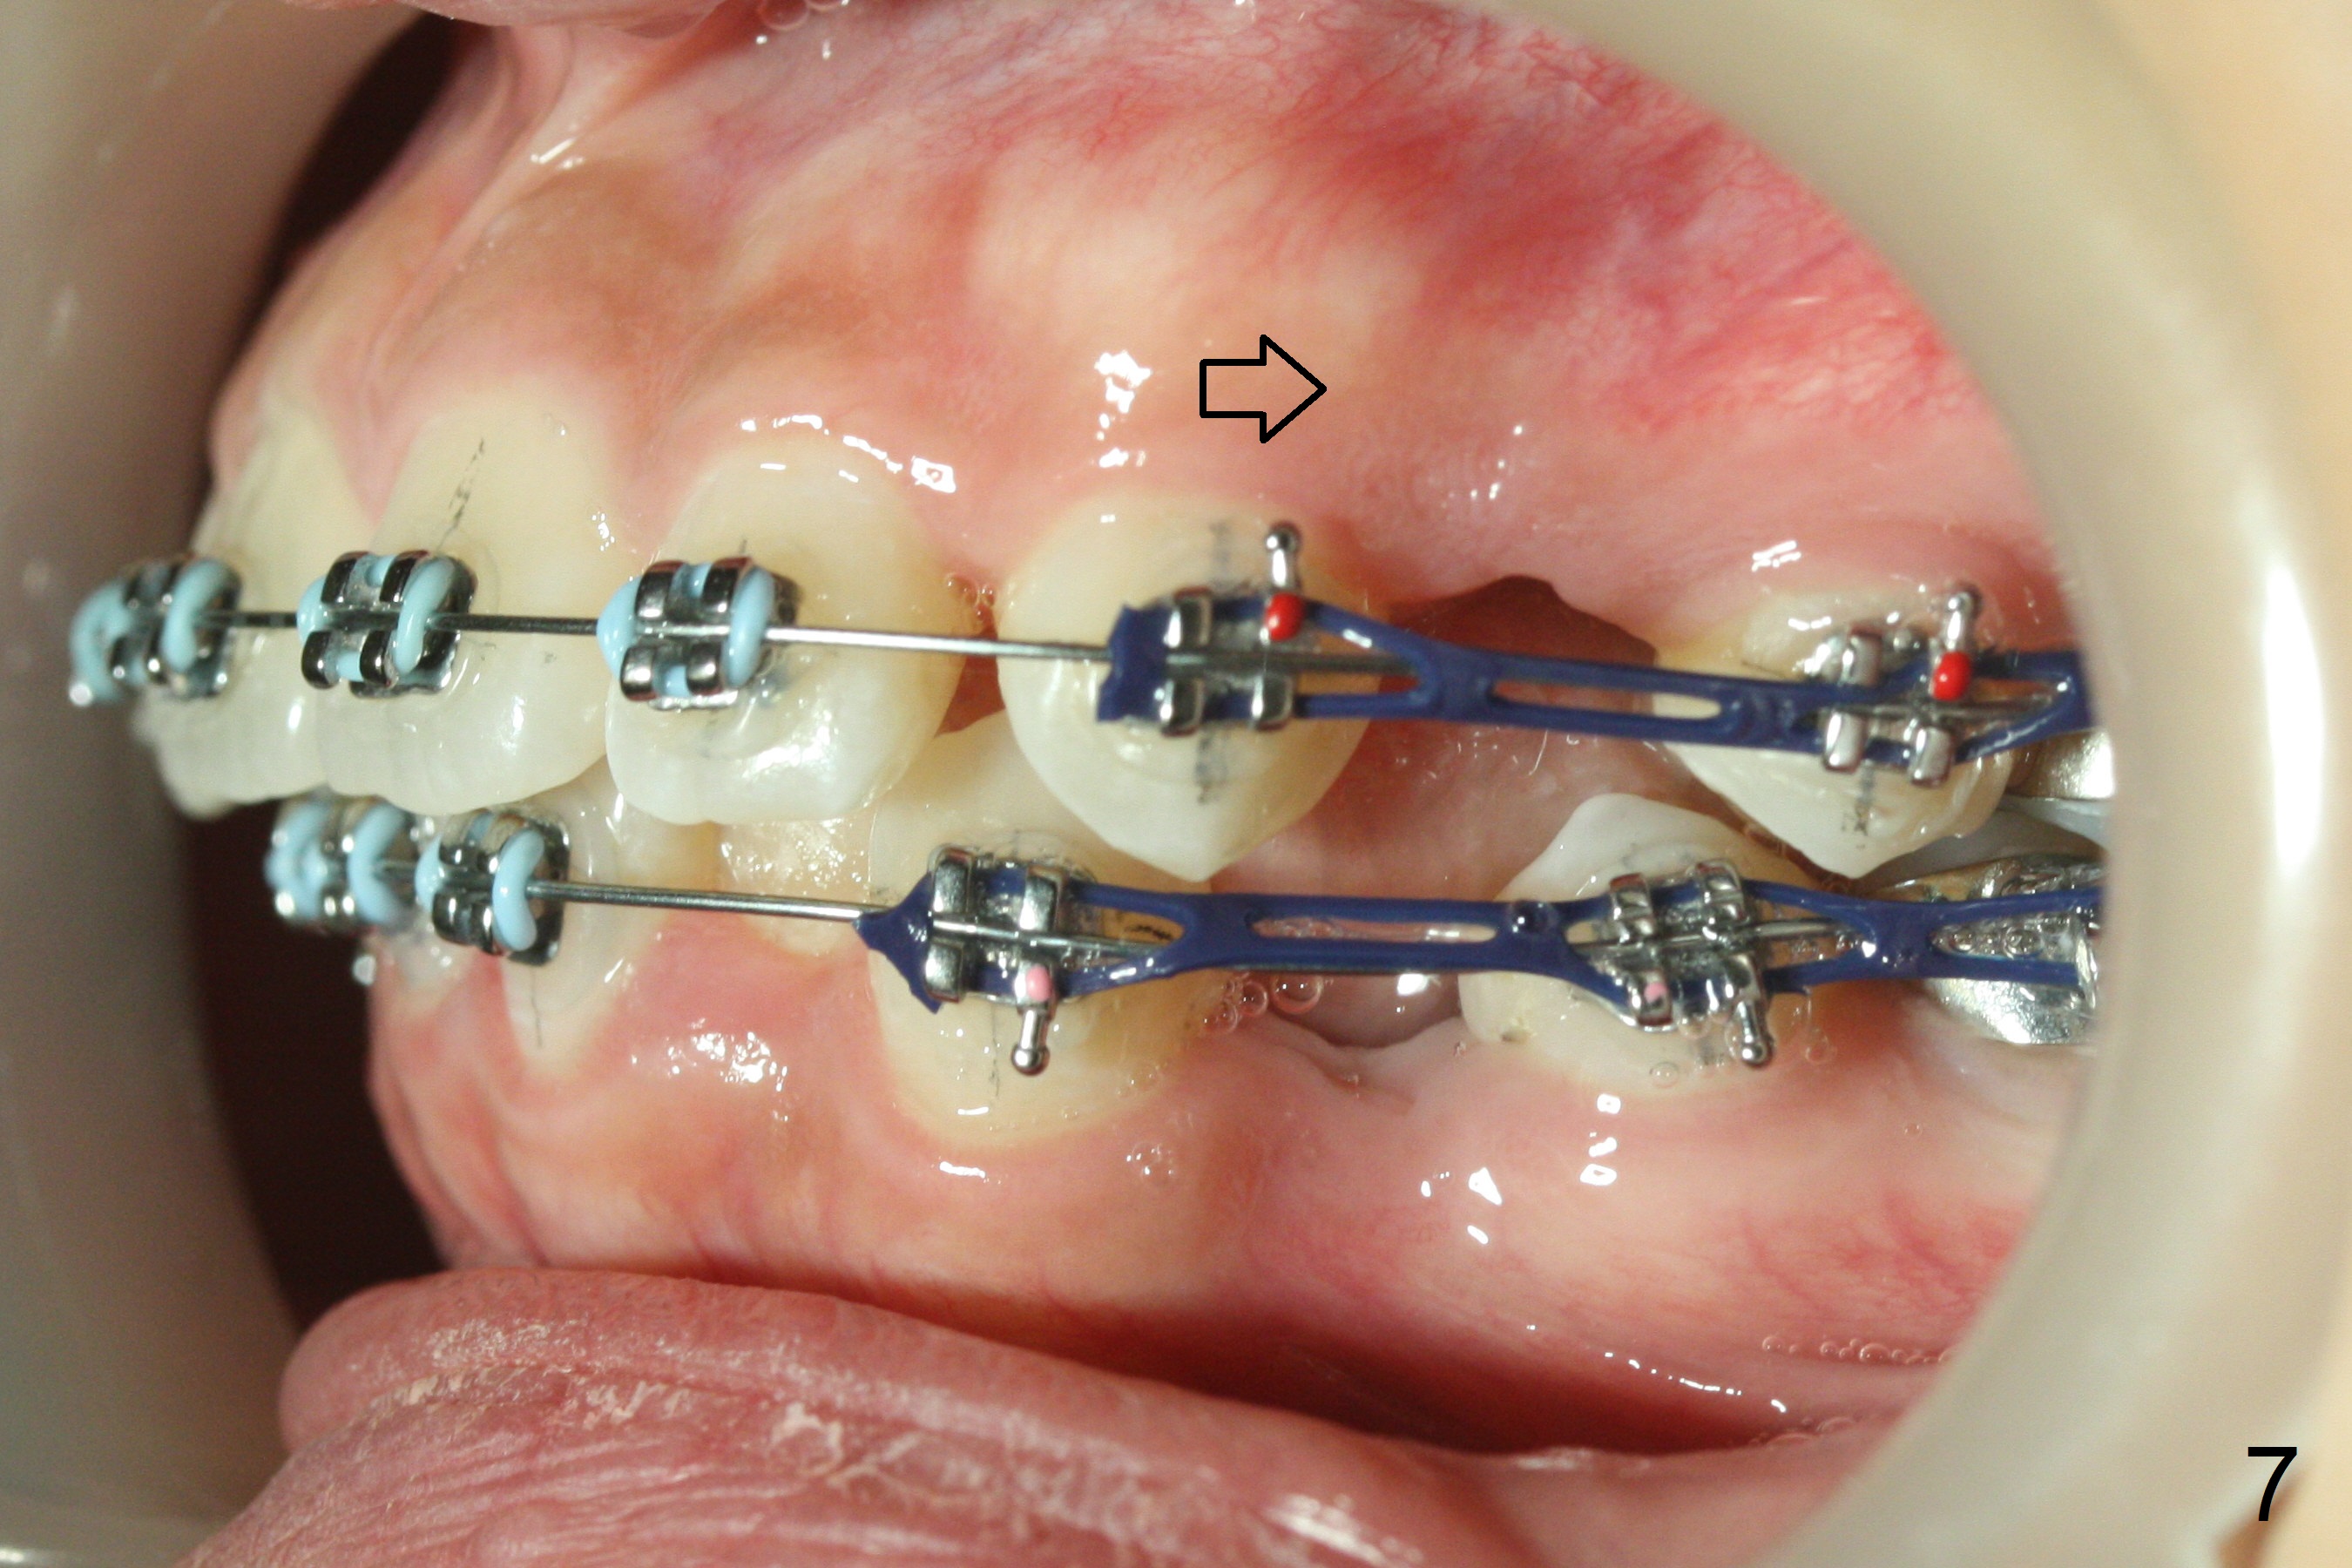

Nearly 3 months post extraction, UL 3 (Fig.7 arrow), LR 3 (Fig.8 *) and UR 3 have distalized by themselves. After changing 16 niti wires, power chains x 4 are placed between 3 and 6 (Fig.7,8) to lay foundation to reduce upper anterior overjet and lower crowding (including LL2 linguoversion). When the space between LR 2 and 3 increases (Fig. 8 *), it will be easy to shift the lower midline (Fig.5) to the right as an open coil spring will be placed between LL 1 and 3. Check the facial and dental midlines next visit before removing the wires.